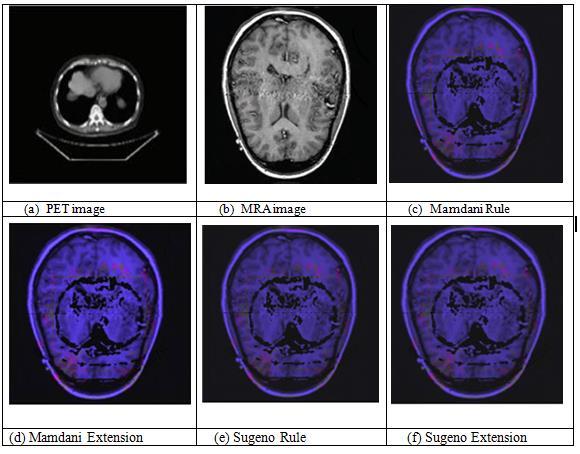

ThefusionfindingsofPETandMRAimagesaredisplayedin Figure6.ThePETinputpictureispicture(a),whiletheMRA input image is Image (b). The fused pictures from the MamdanirulesareshowninImage(c),whilethefusedimages fromtheMamdaniextensionmethodareshowninImage(d). Itisobviousfrompictures(c)and(d)thatthefusedimage producedbyMamdanirulesissubstantiallylessclearthan theonegeneratedbyMamdaniextension.Thefusedimage obtained from the Sugeno extension method is Image (f), while the fused image obtained from the Sugeno rules is Image(e).Ithasbeendemonstratedbythephotos(e)and(f) that the fused image produced by the Sugeno extension is significantlysuperiortotheoutputimageproducedbythe Sugenorules.